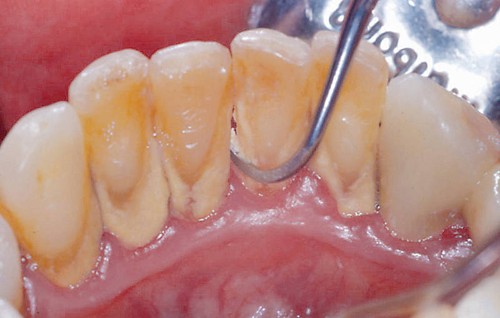

Nguyên nhân phổ biến nhất của viêm lợi là sự tích tụ của mảng bám vi khuẩn giữa và xung quanh răng. Các mảng bám kích hoạt phản ứng miễn dịch, do đó, có thể dẫn đến phá hủy nướu hoặc mô nướu. Cuối cùng, nó sẽ dẫn đến các biến chứng khác.

Mảng bám trên răng là nguyên nhân gây viêm lợi

Mảng bám răng là một màng sinh học tích tụ tự nhiên trên răng. Nó thường được hình thành do vi khuẩn khu trú đang cố gắng bám vào bề mặt nhẵn của răng.

Những vi khuẩn này có thể giúp bảo vệ miệng khỏi sự xâm chiếm của các vi sinh vật có hại, nhưng mảng bám răng lại gây sâu răng và các vấn đề về nha chu như viêm nướu, nhiễm trùng nướu.

Khi mảng bám không được loại bỏ, nó có thể cứng lại thành vôi răng, hoặc cao răng, ở chân răng, gần nướu. Cao răng thường có màu vàng.

Mảng bám và cao răng cuối cùng gây kích ứng nướu, gây viêm nướu quanh chân răng, khiến nướu dễ bị chảy máu.